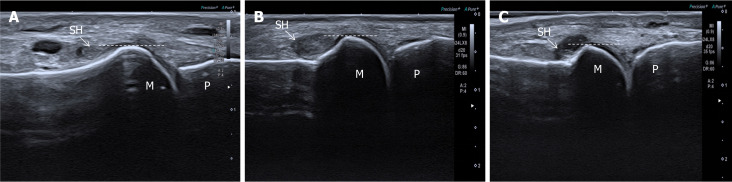

Methods: This cross-sectional study included 56 patients (112 MTPJs) with T2DM from Shenzhen Traditional Chinese Medicine Hospital. Synovial hypertrophy was evaluated using a refined semi-quantitative ultrasound grading system focusing on the dorsal recess overlying the metatarsal bone. Serum 25(OH)D levels were measured. Logistic regression and threshold analyses assessed associations between vitamin D status and hypertrophy severity.